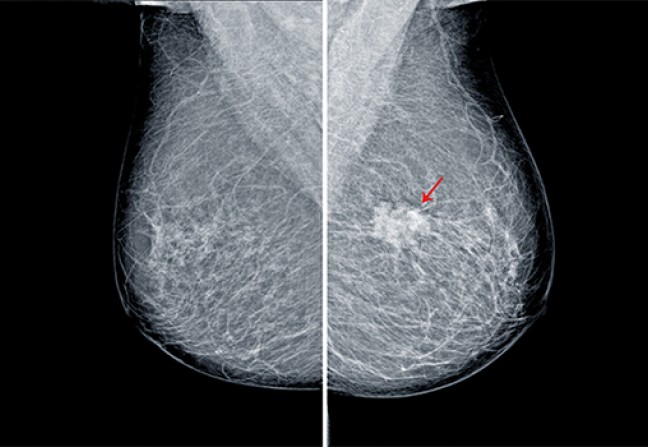

08Point formation n°8

Cette fréquence de la maladie, la possibilité de la traiter, et sa survenue chez des patientes que l’on ne peut identifier a priori ont incité les autorités de santé à mettre en place au début des années 2000 un programme de santé publique. Entre 50 et 75 ans, toutes les femmes sont invitées à bénéficier d’une mammographie tous les deux ans gratuitement.

L’efficacité d’un tel programme sur la diminution de la mortalité des femmes n’est plus à démontrer. Deux clichés radiographiques sont réalisés pour chaque sein et lus par deux radiologues différents. Les conclusions sont rendues à la patiente à l’issue de cette seconde lecture. La patiente est reconvoquée si la mammographie montre une image suspecte, qui nécessite un prélèvement.